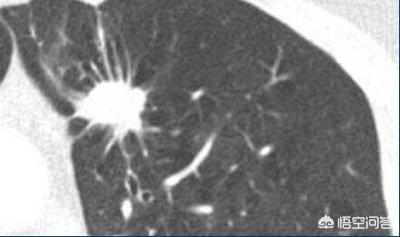

明らかに悪性の徴候のある結節、例えば、小葉状でバリがあり、血液を供給する血管がある結節は、積極的な介入、通常は生検または手術が推奨される。

良性結節や悪性の可能性のある結節など、悪性の徴候を示さない結節に対しては、通常、経過観察が推奨される。良性結節は経過観察中に再吸収したり、変化がなかったりするが、悪性の可能性のある結節は徐々に姿を現すことがあり、悪性結節と同様に治療される。